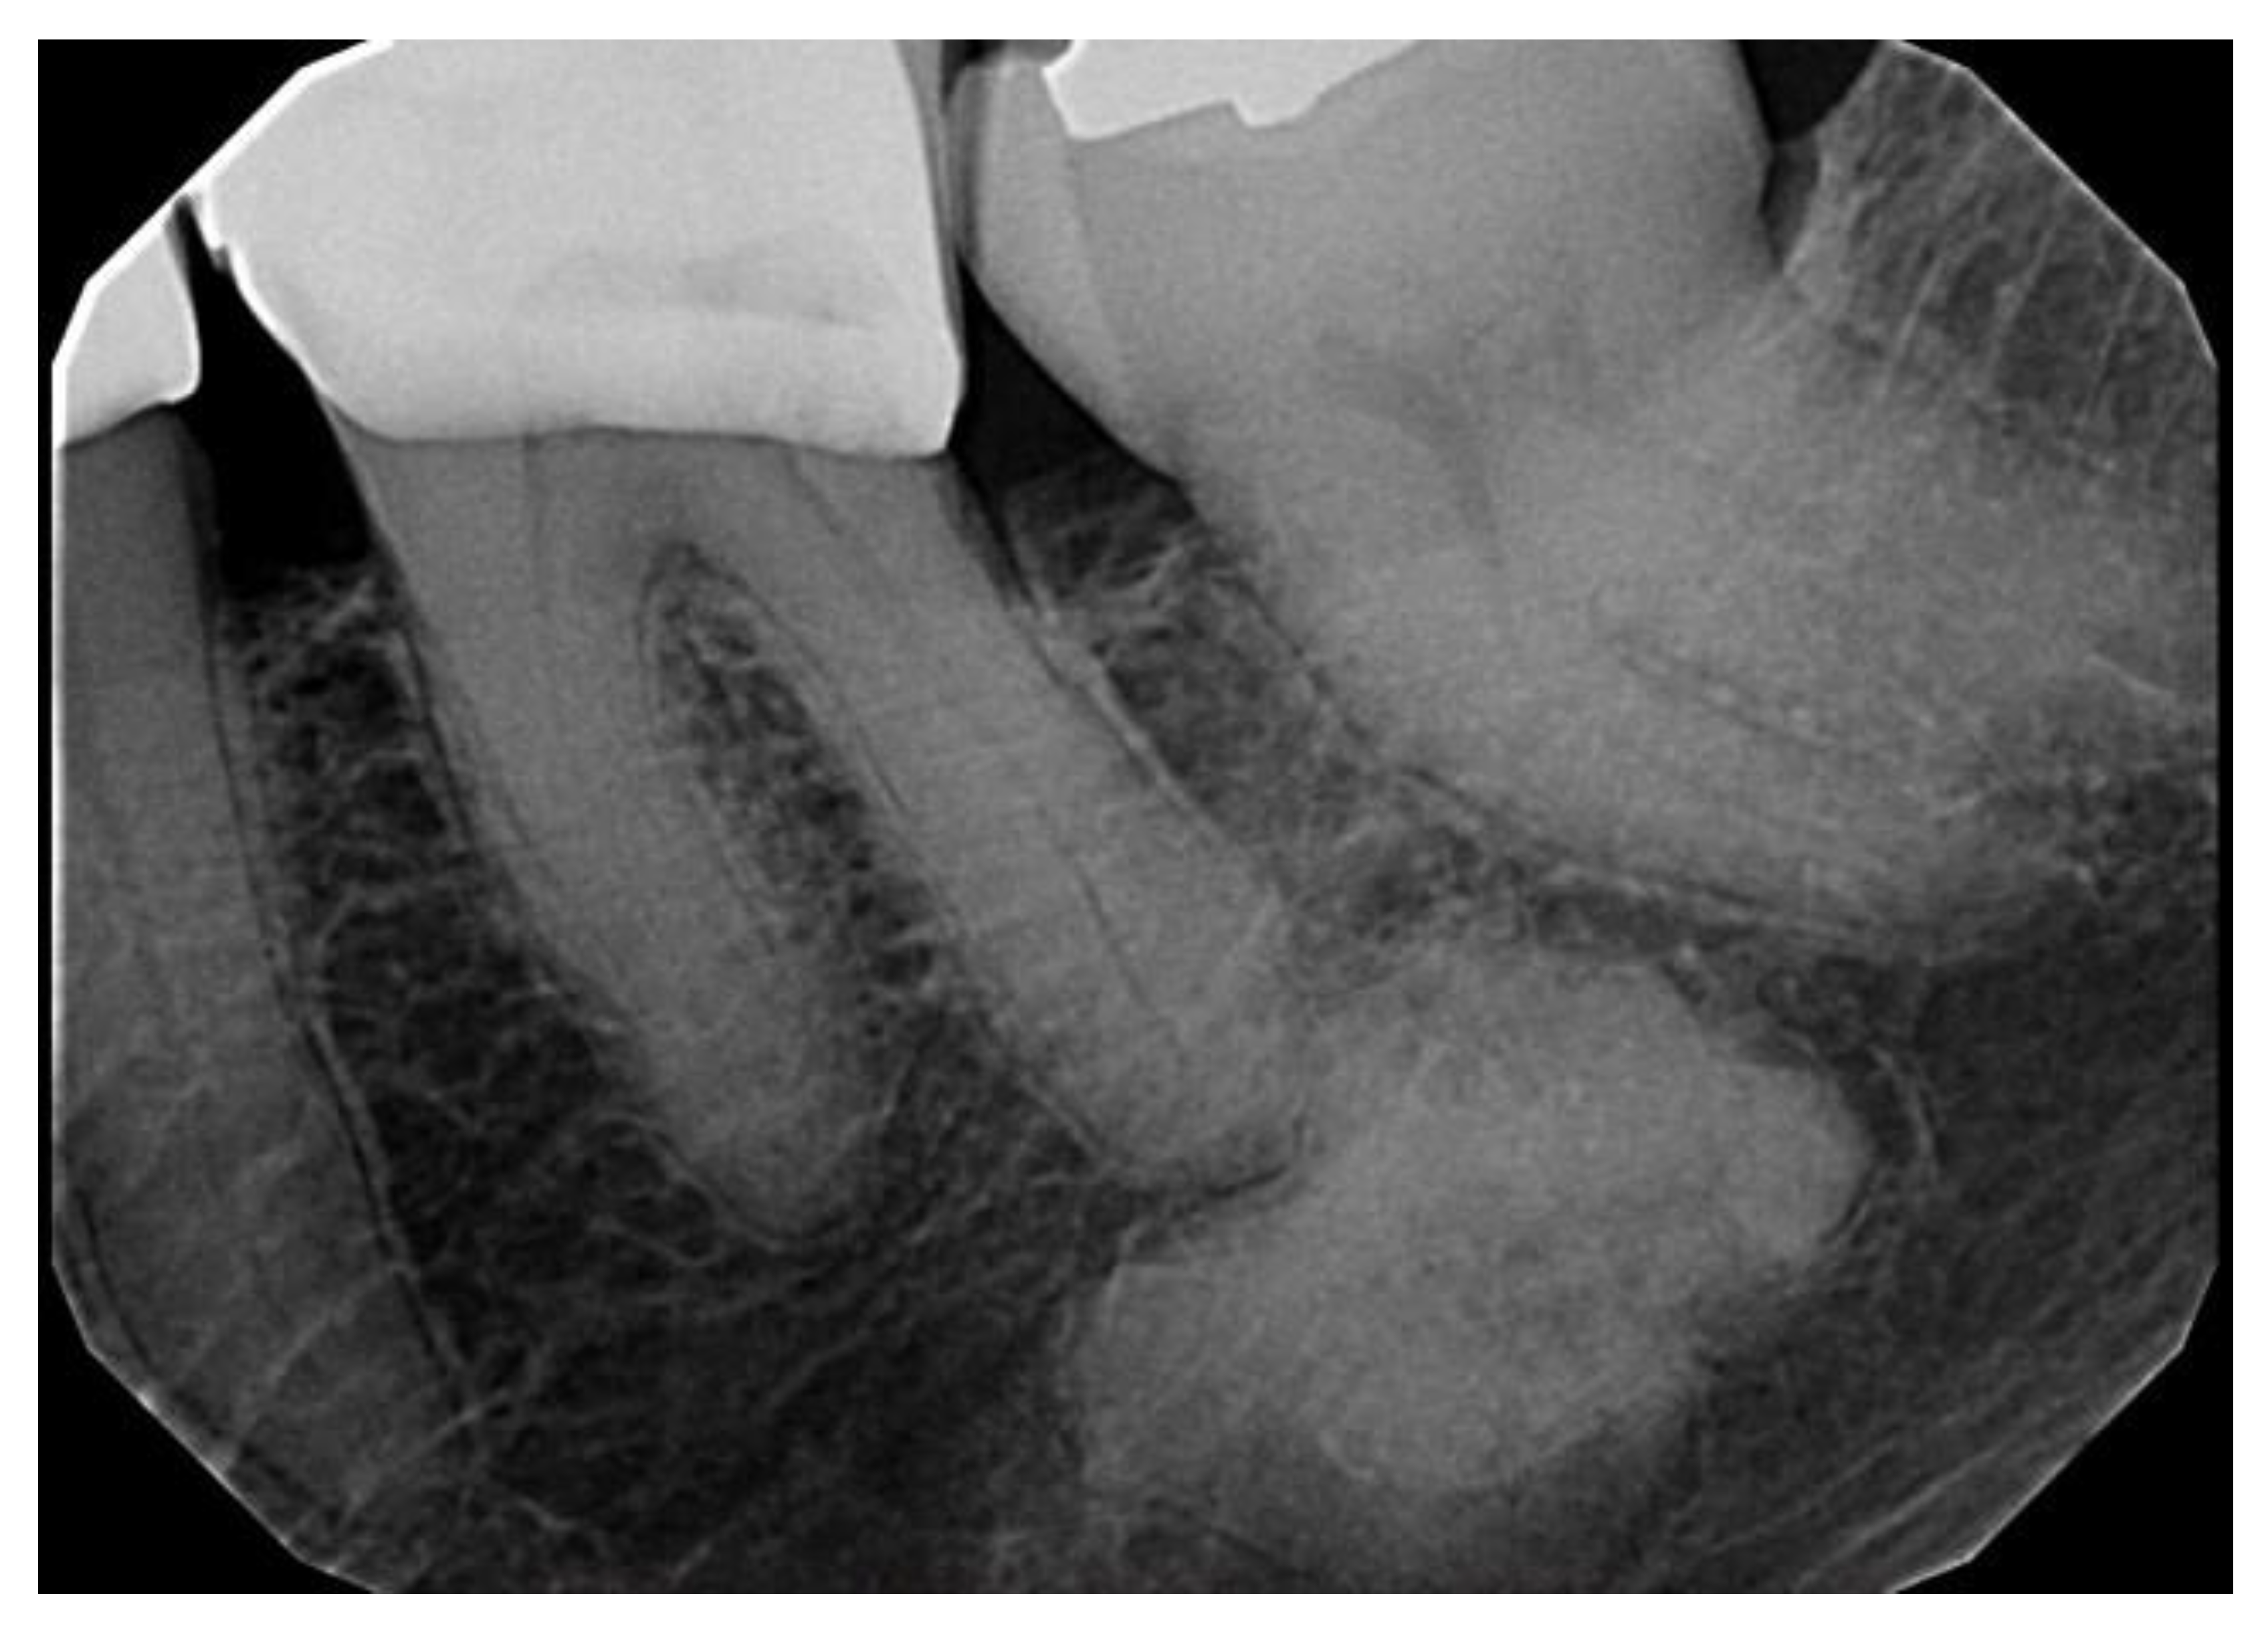

Types of COD